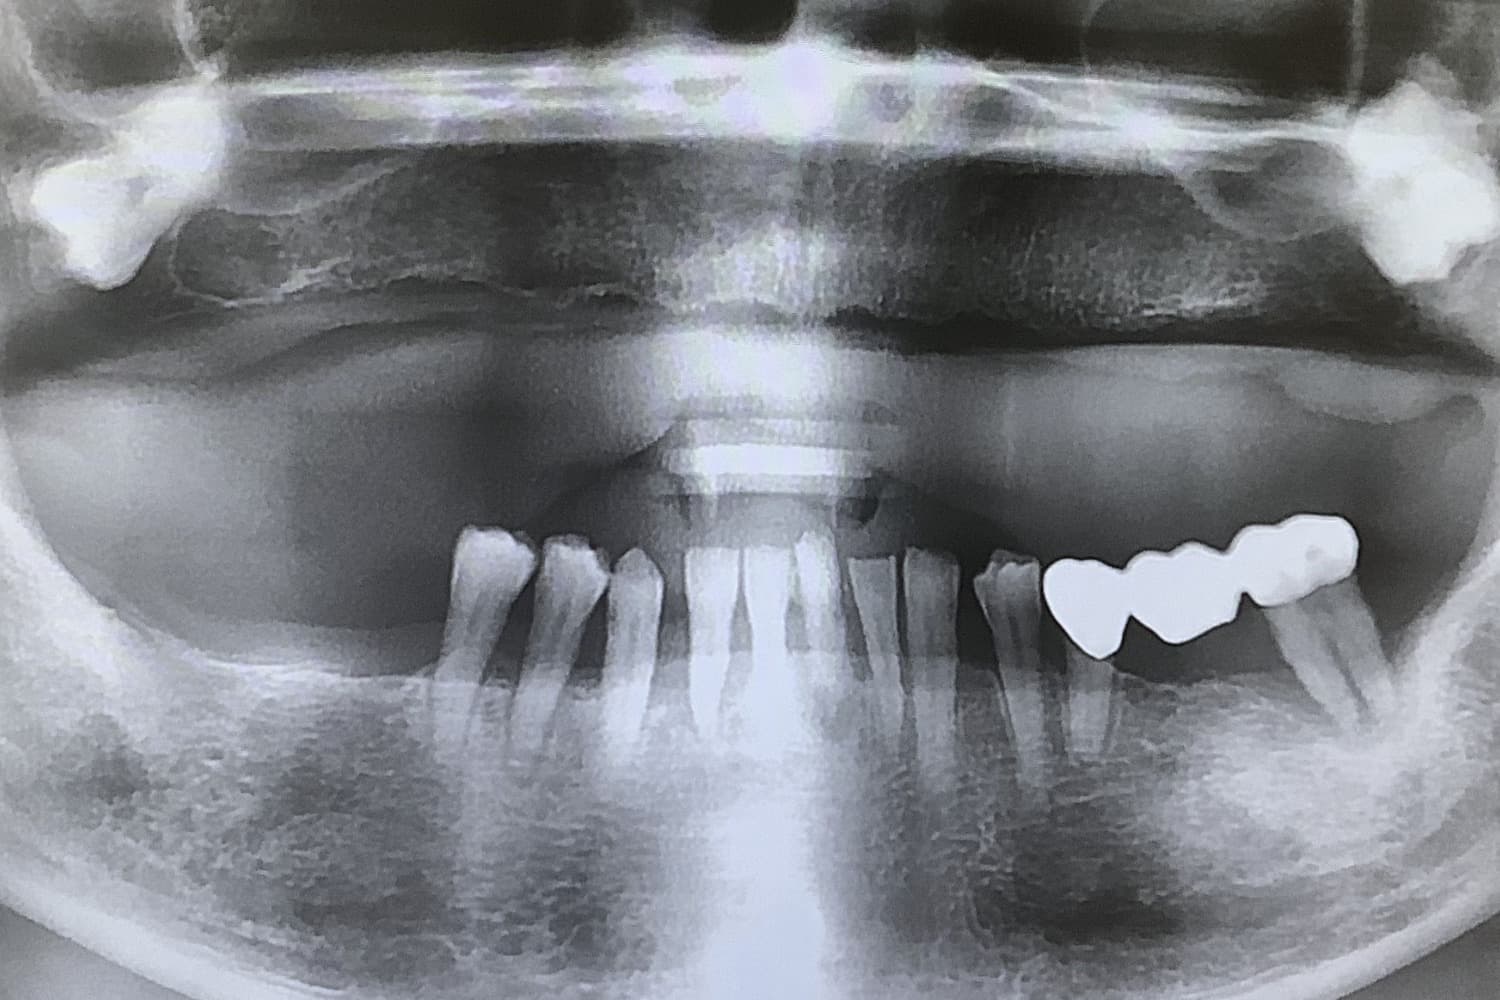

上顎のインプラント治療

上顎に8本インプラントを埋入手術しブリッジ冠を用いて修復した

年齢

50

性別

男性

主訴

上顎の総入れ歯が嫌なのでインプラントにしたい

治療期間

8ヵ月

治療回数

8回

費用

2,860,000円

副作用・リスク

・全身疾患の有無や骨の状態によってインプラント体が骨と生着しない可能性がある ・術後患部が腫れたり痛みが生じたりする可能性がある